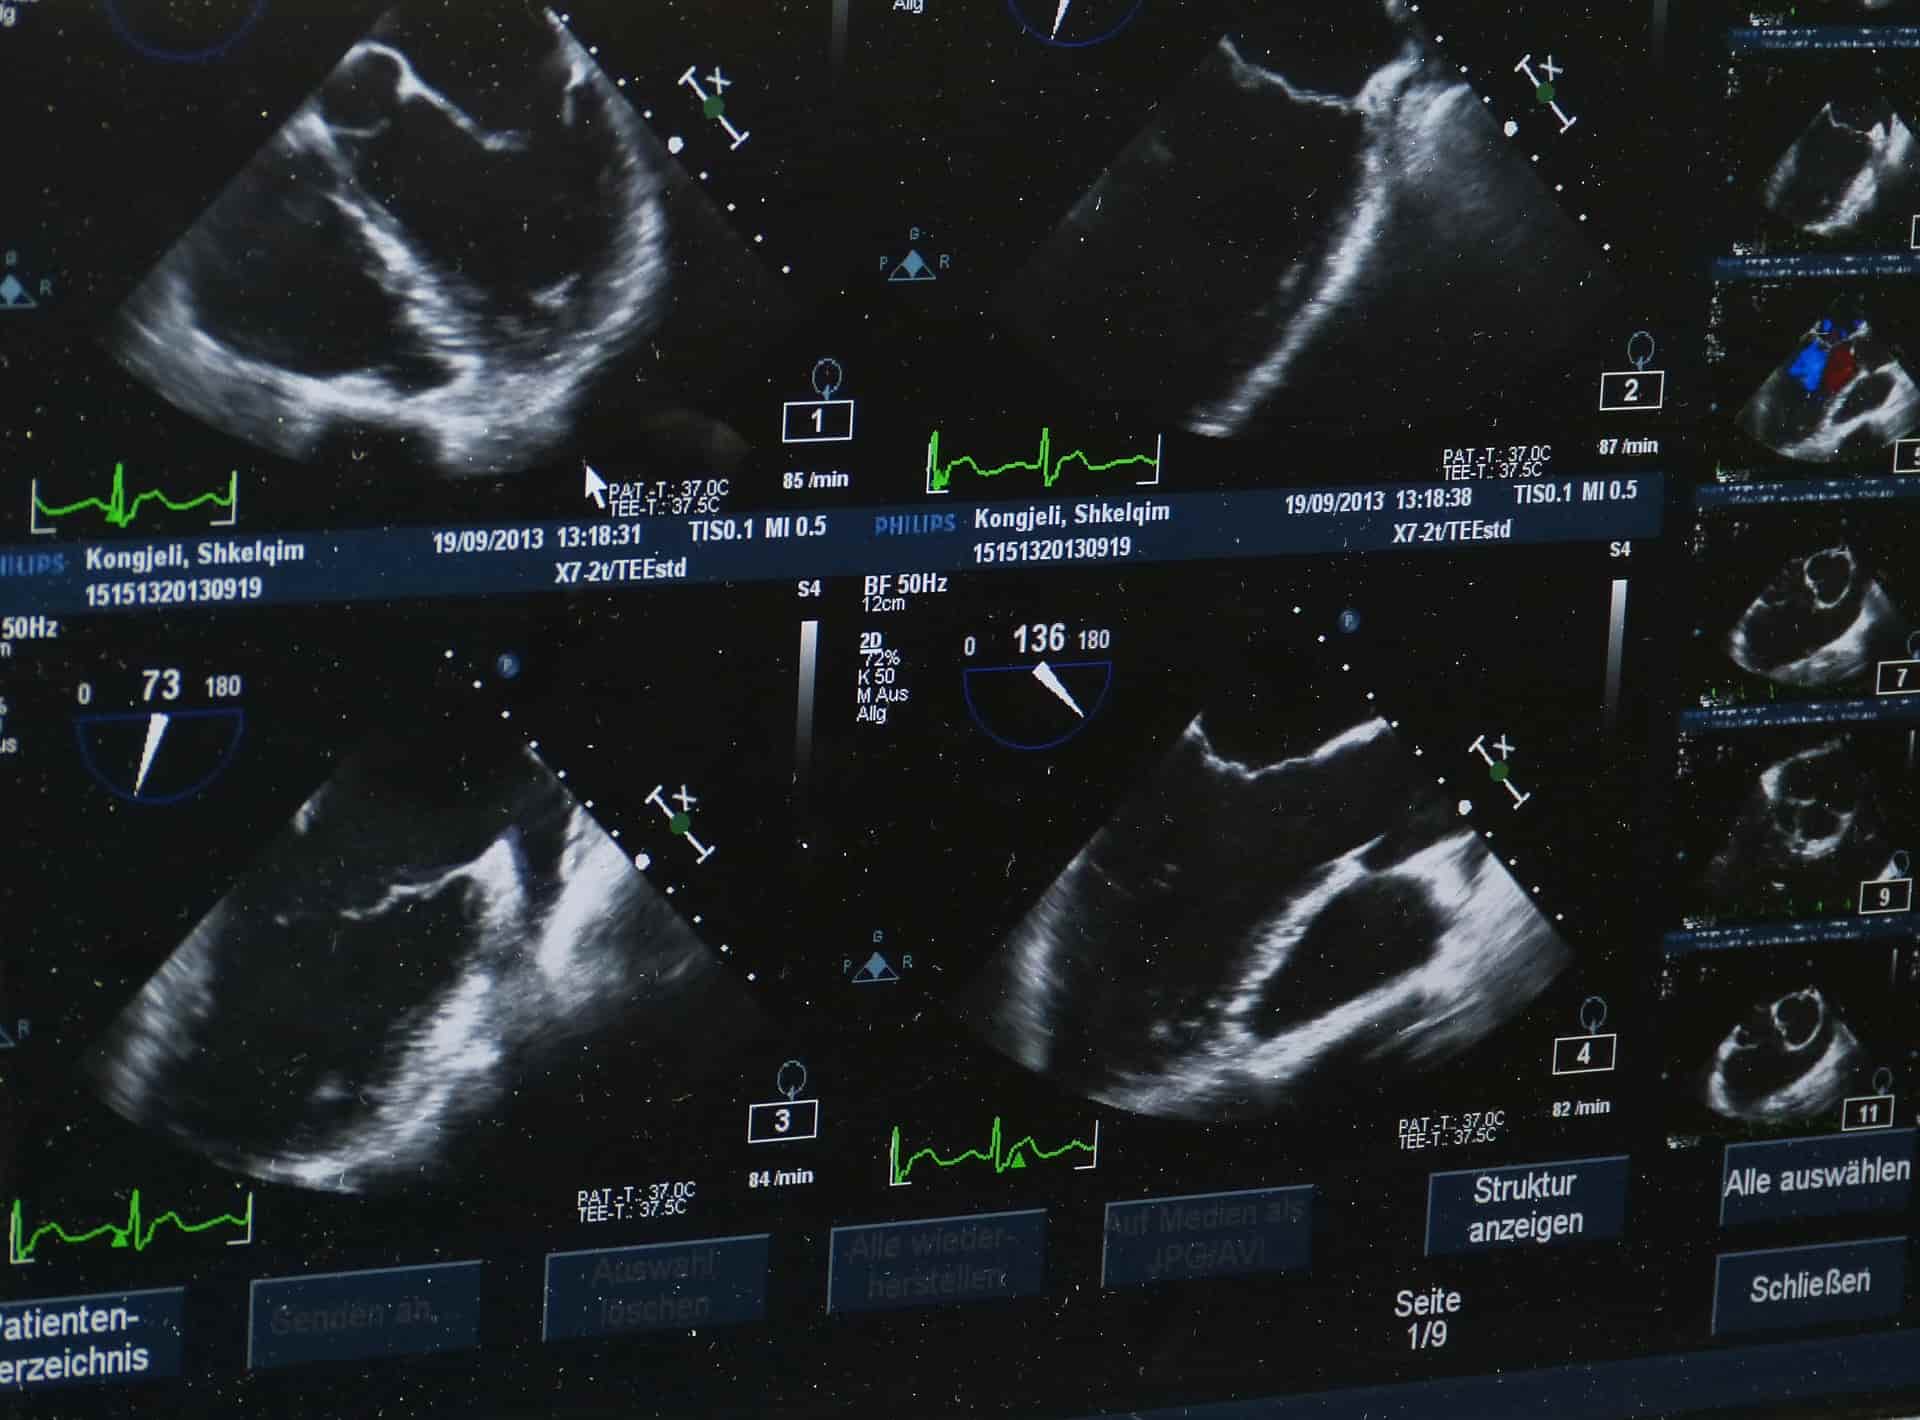

シーズン1 第2話 THE ONE WITH THE SONOGRAM AT THE END

sonogram

タイトル:THE ONE WITH THE SONOGRAM AT THE END

sonogram超音波画像

対訳)最後に超音波画像が出てくる話